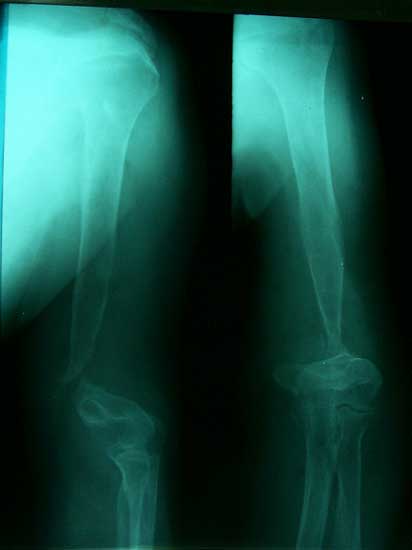

肱骨骨折,3次钢板和钢丝固定后失败。改用带锁髓内钉固定,4个月后骨折愈合。